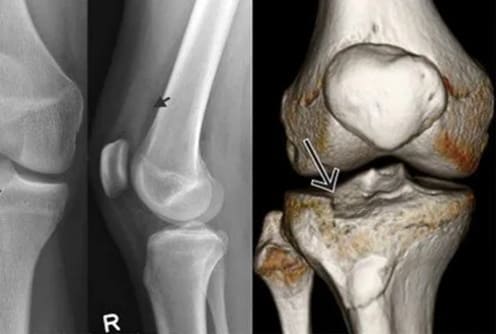

Cuando veas esto en una radiografía, tu articulación ya no podrá recuperarse.

PASO 2: SENTENCIA PARA TU ARTICULACIÓN

Así es como se ve el punto sin retorno.

Lo que el médico verá en la imagen:

ESPACIO ARTICULAR COMPLETAMENTE AUSENTE

El hueso roza contra el hueso.

OSTEOFITOS

La articulación está deformada por crecimientos óseos afilados.

El movimiento se bloquea.

ATROFIA MUSCULAR

Los músculos se debilitan y ya no sostienen la articulación.